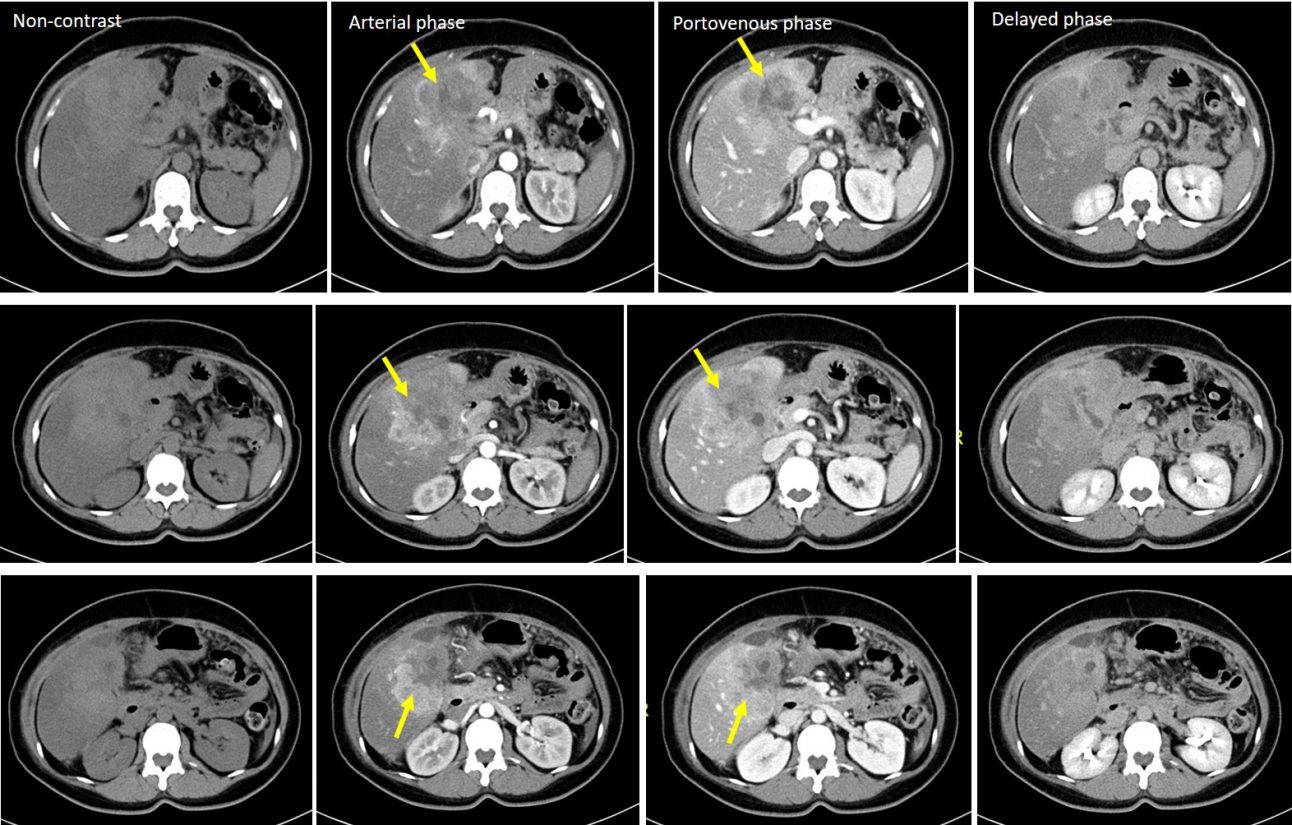

Massforming cholangiocarcinoma Radiology Case RadioGyan Cholangiocarcinoma Eovist Radiology — gadoxetate disodium (also known by the tradenames primovist in europe and australia/new zealand and eovist in the united states) is a. Cholangiocarcinoma Eovist Radiology.